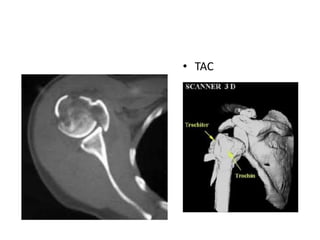

ESTUDIOS DIAGNOSTICOS

• AP DE HOMBRO

VERDADERA

• TRANSTORACICA

• PERFIL ESCAPULAR

• TAC

• RESONANCIA

MAGNETICA

ESTUDIOS DIAGNOSTICOS • APDE HOMBRO VERDADERA